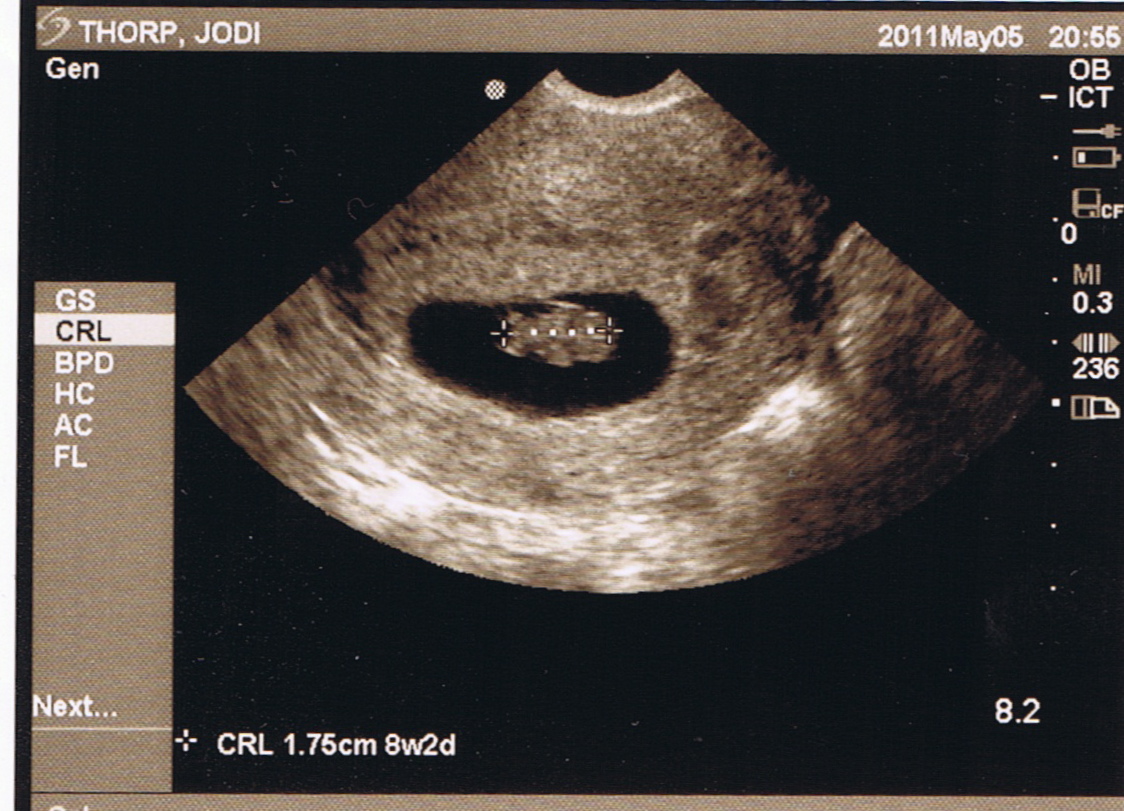

The photo above was the highlight of the hour or more we spent in a dimly lit room with the sonographer. It was worth the wait, but to be honest, I was more excited about these two images:

These show our baby at just eight weeks of development. We’re looking down on him or her from above, with an absolutely Thorpian head to the right, and a torso with four tiny limbs extending to the left and down in the lower image. This was a thrill, not only because we lost a little one last fall and were hoping for an “all systems go!” from our doctor, but because there on the screen was a tiny person, less than two centimeters long, with a beating heart and legs and arms that moved independently of any thought or command from Jodi or me. A child the size of my fingertip who, just before Christmas, we will be blessed to welcome and trusted to raise.

This was made clear again to me when I saw our tiny infant, wriggling in amniotic bliss, at eight weeks of development. Jodi had no say in the flailing of those tiny arms and legs, and that tiny heart beat in part because of, but not for, her. No choice on her part, short of violence, could have stopped it.